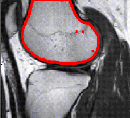

Region based segmentation with levelsets

Edge based segmentations are intuitive since edges usually show an object boundary. However in some or many cases, edges are not sharp or are simply not there. Region based segmentations is a solution to this problem. Here is an example using a level set framework.